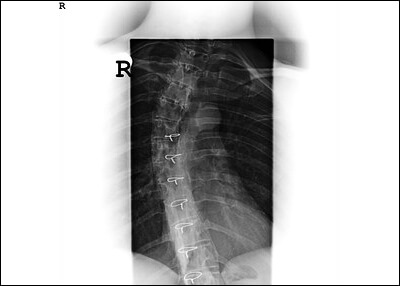

석회건염은 회전근의 노화로 인한 퇴형성 질환이라고 할 수 있습니다. 석회가 생겨서 힘줄 내부를 팽창시켜 통증을 유발하게 되므로 되도록 빠른 시간 내에 병원에 방문해서 치료를 받는 것이 좋습니다. X-레이나 초음파로 바로 확인할 수 있으며 주사요법, 체외 충격파 치료 등으로 치료합니다.